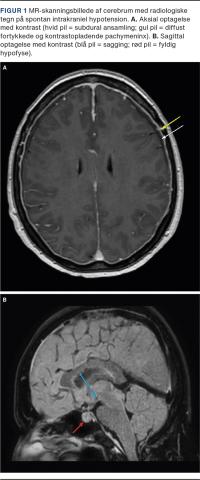

Den neurologiske undersøgelse, hendes almentilstand, ekg, vitalparametre og blodprøvesvar var upåfaldende. CT af hjernen viste bilaterale smalle, subdurale ansamlinger uden tegn på friske blødningskomponenter. MR-skanning af hjernen og rygmarven med intravenøs kontrast viste nedsynkning af mesencefalon og hjernestammen (sagging, pontomesencefal vinkel reduceret til 45 grader), en lidt fyldig hypofyse, diffust fortykkede og kontrastopladende pachymeninx intrakranielt (Figur 1) og intraspinalt samt et let øget epiduralrum torakalt. Hun blev på mistanke om SIH behandlet med lumbal epidural blood patch (EBP) med eklatant effekt.

Klassiske fund på cerebral MR-skanning er sagging, diffust pakymeningeal kontrastopladning, hygromer, subdurale hæmatomer, forstørret hypofyse og prominente sinus, men fundene er ikke altid til stede [4]. Hos patienten i sygehistorien blev der ikke gennemført lumbalpunktur, da det ikke er påkrævet for diagnosekriterierne, men behæftet med risiko for forværring af SIH samt diagnostisk usikkerhed, idet åbningstrykket ikke sjældent er normalt [3, 5].